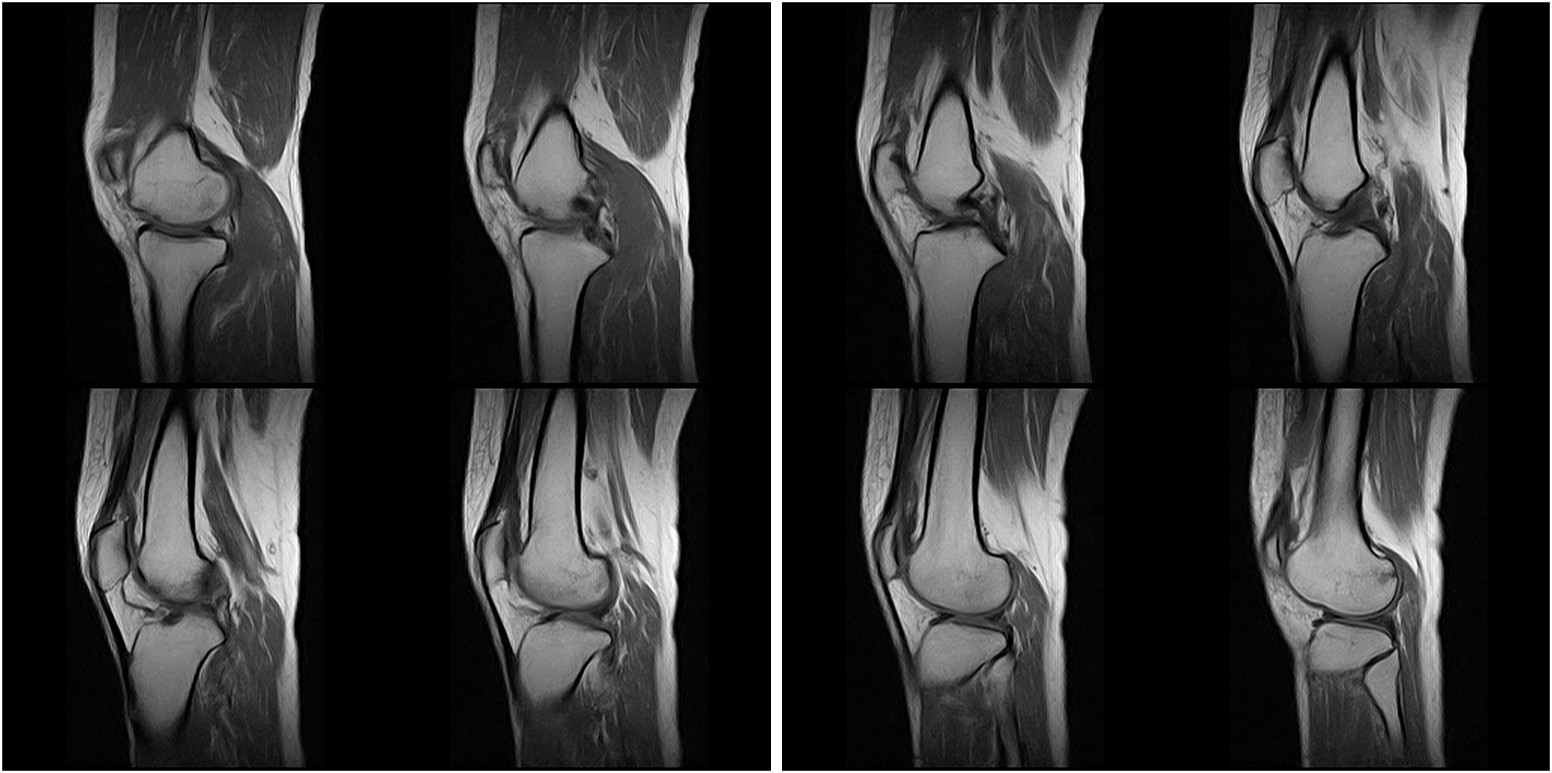

Hình ảnh lâm sàng

Giải pháp lâm sàng ấn tượng